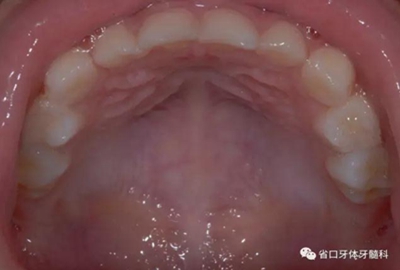

圖7 上頜牙相

8.jpg